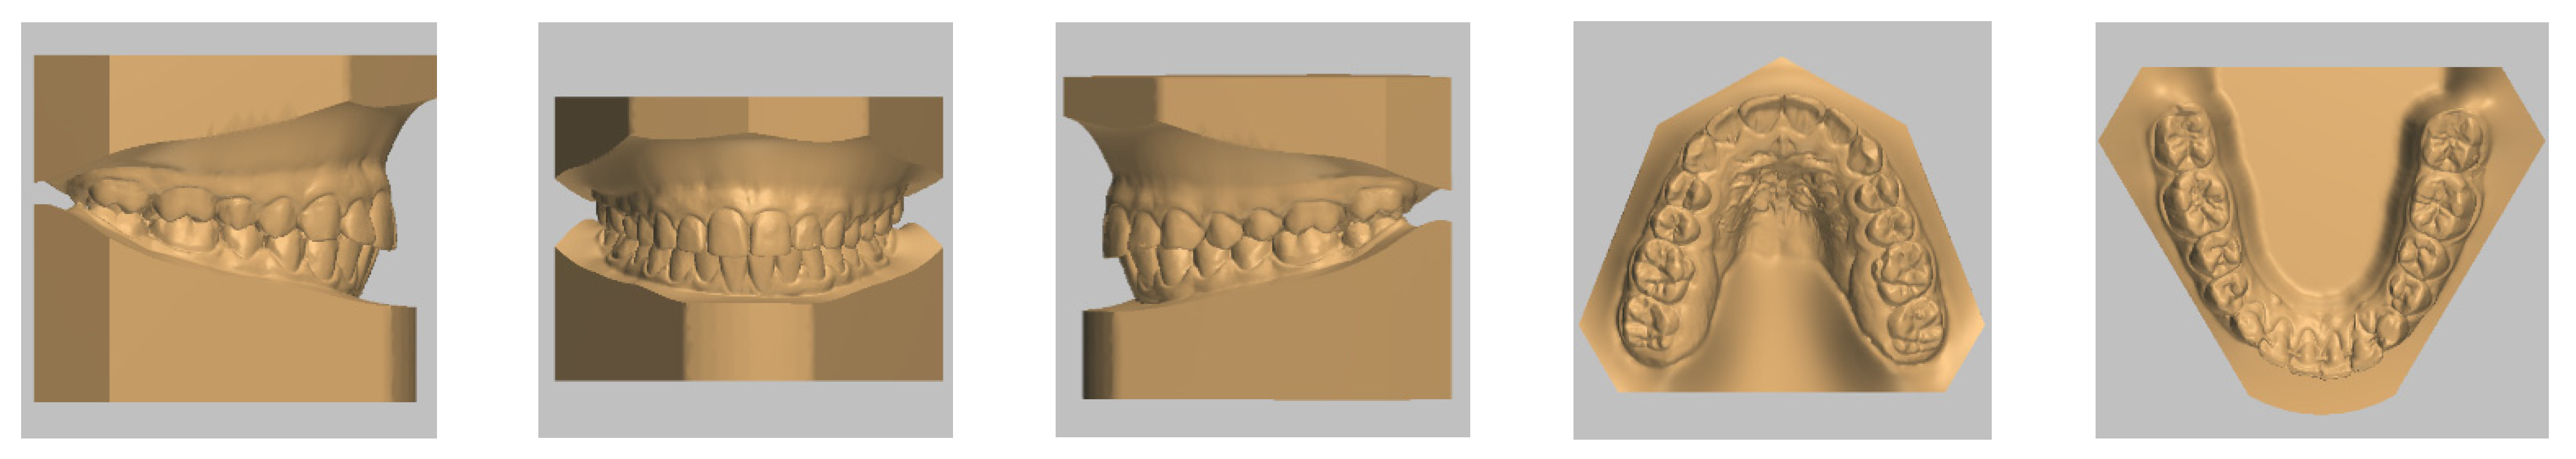

4. Case Report

4.1. Etiology and Diagnosis

4.2. Treatment Objectives

4.3. Treatment Strategy

4.4. Treatment Progress